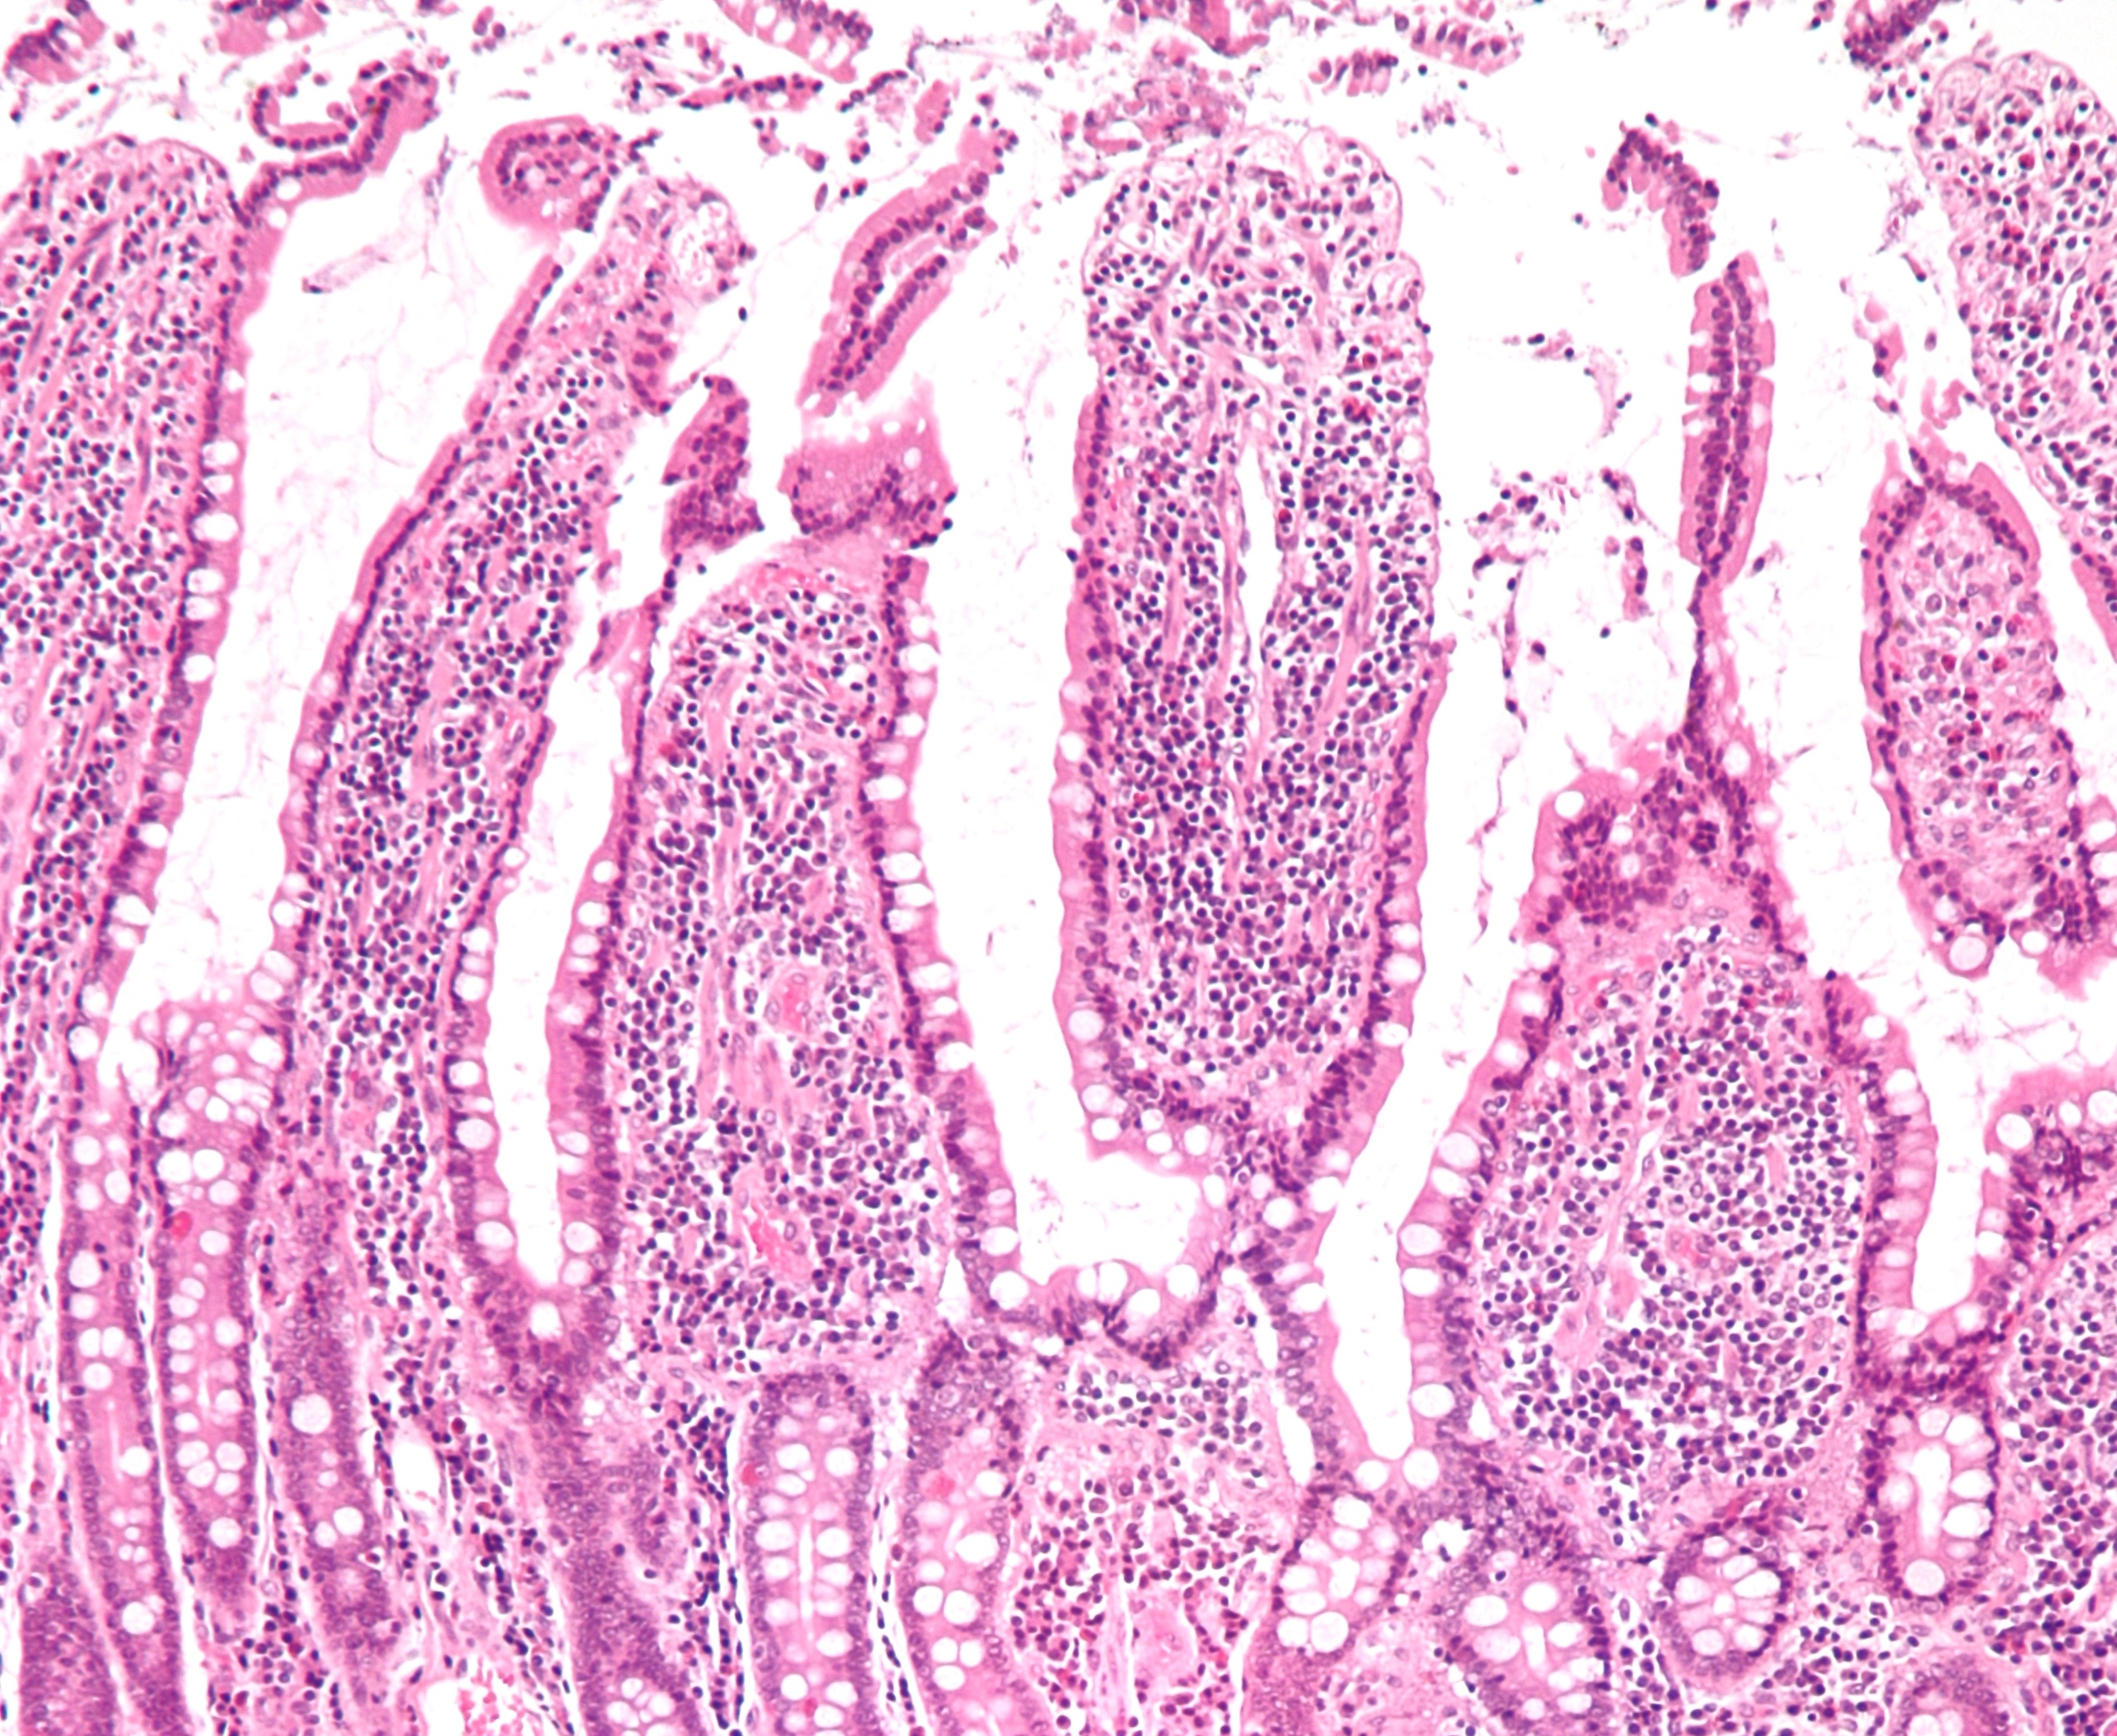

Photo hosted on Wikimedia Commons, CC BY-SA 2.0

Instead, much of the surface area of the gut comes from tiny structures on the inner surface of the gut. The inner surface is wrinkled, which helps increase surface area. Furthermore, it’s covered with weird, tentacle-like microscopic structures called villi. Then each villus itself is covered with tentacly microvilli. Villi and microvilli are evolutionary adaptations that help the body absorb nutrients. Scientists have long known about them.

Fändriks and Helander took biopsies from healthy human volunteers (in perhaps one of the kindest contributions made to basic science) to examine these villi and microvilli. The researchers used light and electron microscopes to take images of the inner-gut structures. They calculated how the structures increased the simple surface area the researchers could calculate from the lengths and diameters of people’s intestines.